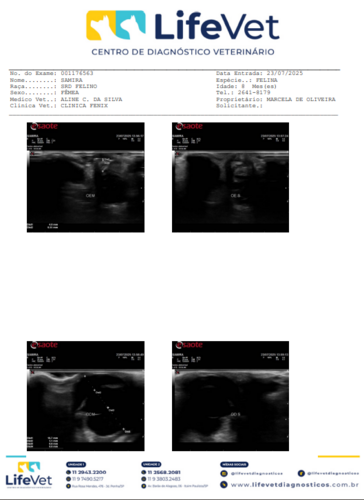

Anexo está o exame de ultrassom realizado, comprovando a necessidade da cirurgia.